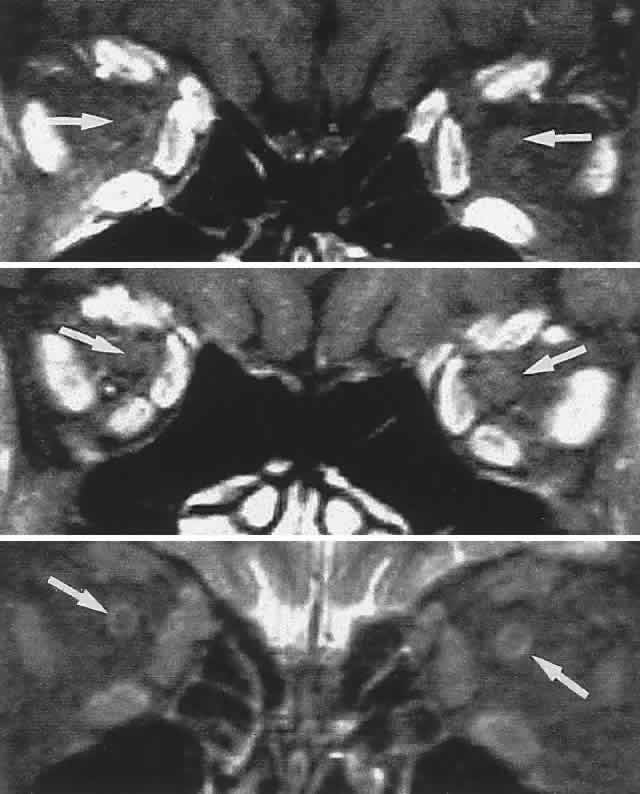

Graves' disease is the overwhelming single most common cause of single or multiple extraocular muscle thickening (Fig. 18; see also Volume 2, Chapter 12, Figs. 28 and 30); inflammatory myositis is considerably less frequent, and muscle metastases are quite rare. Passive congestive myopathy also accompanies arteriovenous shunts and lesions of the superior orbital fissure and cavernous sinus, where orbital venous return is obstructed. The capacity of CT to detect minor to moderate changes in muscle diameter is perhaps limited,70 and standardized A-scan ultrasonography seems more sensitive and practical.71

Fig. 18. CT scan in Graves' disease. Top. Axial section shows massively enlarged horizontal recti (M, medial) with packed apex. Bottom. Coronal section demonstrates enlarged medial (M), superior (S), and inferior (I) recti.

Now almost universally available, MRI is the preferable technique for imaging the soft tissue contents of the orbit, high-resolution 3-mm and thinner sections being available, as well as gadolinium contrast enhancement (Figs. 19, 20, and 21).

Fig. 19. MRI of orbits, axial sections. Top. T1-weighted: orbital fat is white (hyperintense), muscles are dark. Middle. Fat saturation with gadolinium through midorbit: orbital fat signal suppressed (dark), accentuates hyperintense muscles; note also choroid (small arrows). Bottom. Fat-saturation technique through superior aspect of orbit; note superior ophthalmic veins (arrows).

Fig. 20. MRI of orbits, coronal sections. Fat suppression. Top. Midorbit. Middle. Orbital apex. Bottom. T2-weighted. Arrows indicate optic nerve; note ring of CSF (bottom).